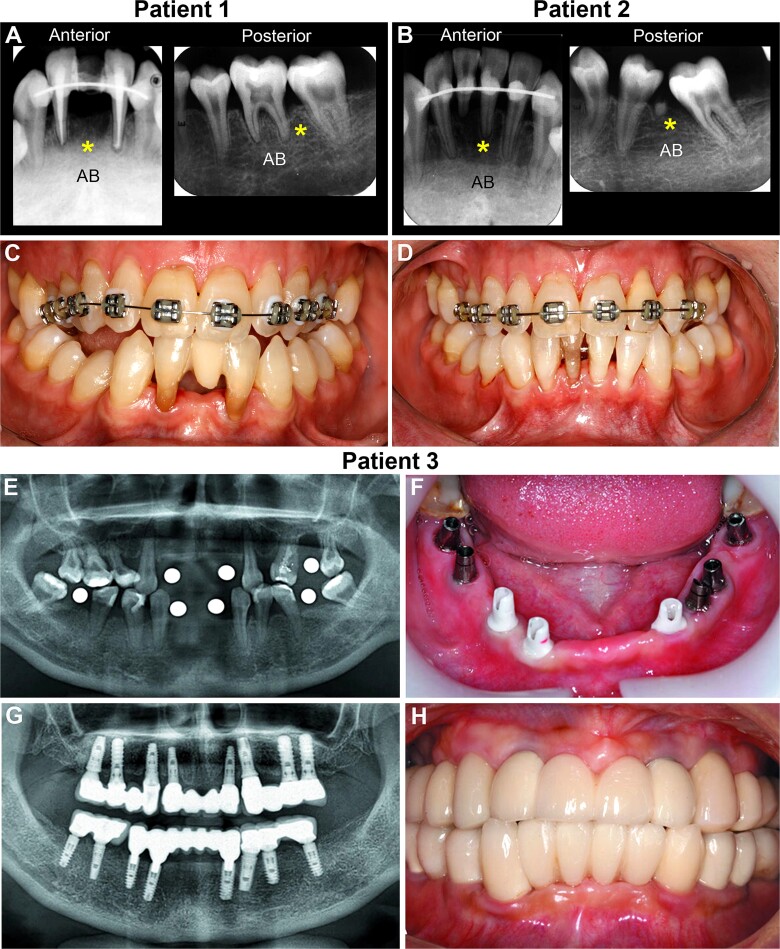

Hypophosphatasia (HPP) is an inherited error in metabolism resulting from loss-of-function variants in the ALPL gene, which encodes tissue-nonspecific alkaline phosphatase (TNAP). TNAP plays a crucial role in biomineralization of bones and teeth, in part by reducing levels of inorganic pyrophosphate (PPi), an inhibitor of biomineralization. HPP onset in childhood contributes to rickets, including growth plate defects and impaired growth. In adulthood, osteomalacia from HPP contributes to increased fracture risk. HPP also affects oral health. The dentoalveolar complex, that is, the tooth and supporting connective tissues of the surrounding periodontia, include 4 unique hard tissues: enamel, dentin, cementum, and alveolar bone, and all can be affected by HPP. Premature tooth loss of fully rooted teeth is pathognomonic for HPP. Patients with HPP often have complex oral health issues that require multidisciplinary dental care, potentially involving general or pediatric dentists, periodontists, prosthodontists, and orthodontists. The scientific literature to date has relatively few reports on dental care of individuals with HPP. Animal models to study HPP included global Alpl knockout mice, Alpl mutation knock-in mice, and mice with tissue-specific conditional Alpl ablation, allowing for new studies on pathological mechanisms and treatment effects in dental and skeletal tissues. Enzyme replacement therapy (ERT) in the form of injected, recombinant mineralized tissue-targeted TNAP has been available for nearly a decade and changed the prognosis for those with HPP. However, effects of ERT on dental tissues remain poorly defined and limitations of the current ERT have prompted exploration of gene therapy approaches to treat HPP. Preclinical gene therapy studies are promising and may contribute to improved oral health in HPP.